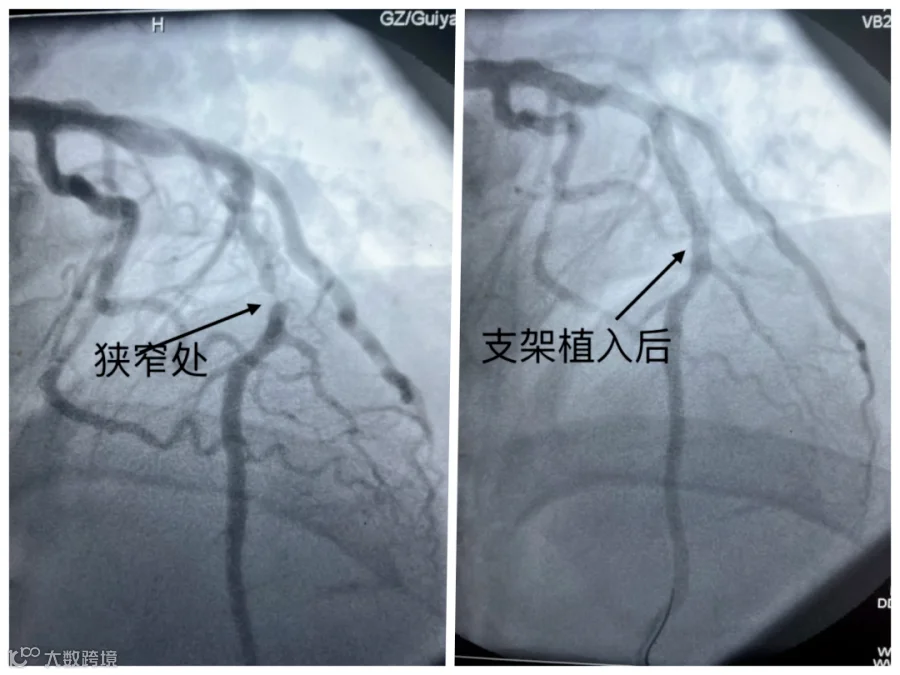

2024年5月23日,来自贵州52岁的李先生

出现牙痛并伴随不明显的胸痛

,他以为是牙病犯了,便自行服用“甲硝唑”等消炎止痛药,但未见好转。不料四天后的凌晨,李先生的牙痛和胸痛突然加剧,全身冒汗,遂就医。

医生为其进行心电图检查,结果提示

急性广泛前壁心肌梗死

。

随后,医生在其狭窄血管处植入支架,李先生转危为安。